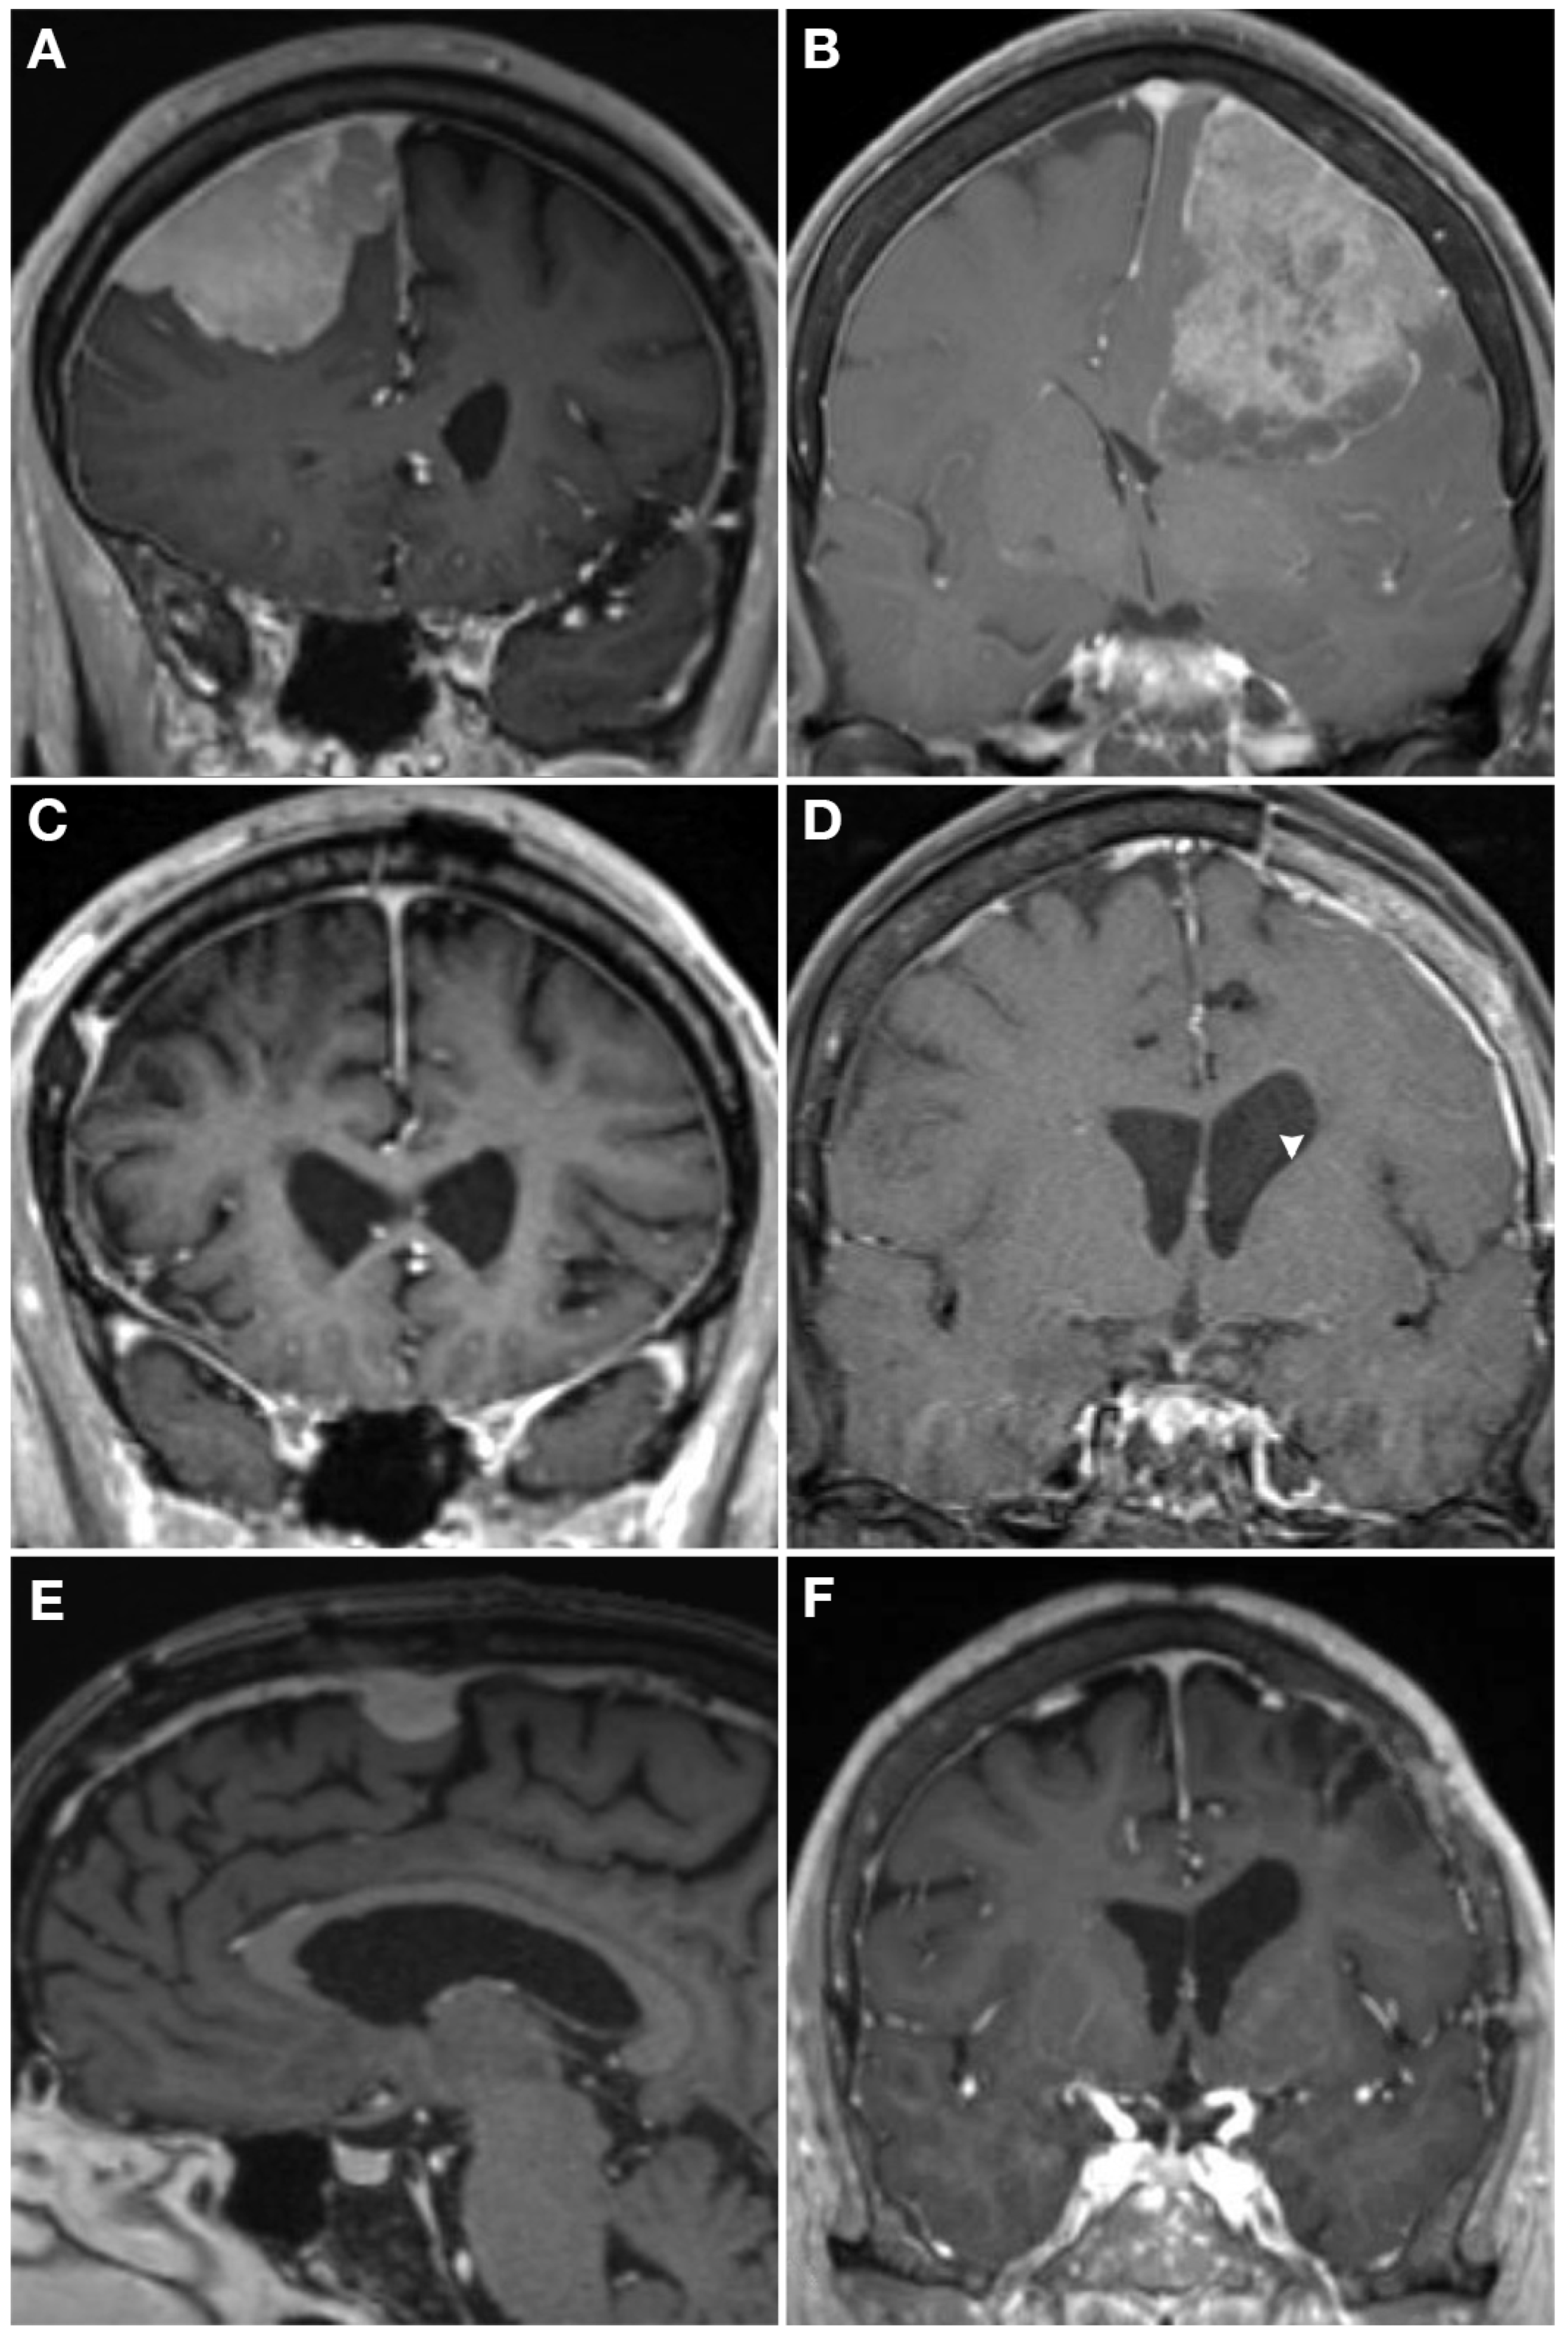

健康・医学 Meningiomas, Part II (Volume 170) i2 Meningiomas。Regression of Intracranial Meningiomas Following Treatment。Unveiling a Biomarker Signature of Meningioma: The Need for。Meningiomas, Part II (Volume 170) (Handbook of Clinical Neurology, Volume 170) ハードカバー – 2020/8/14英語版 Michael W. McDermott MD (編集)※中古品のため、使用できれば良いという方のみのご購入をお待ちしております。筋骨格系のキネシオロジー。※商品状態の少々の見落としはご理解下さい。骨形態計測ハンドブック/高橋栄明 著。※都合により発送方法を変更する場合があります。【美品・書き込みなし】精神薬理学エセンシャルズ/精神科治療薬の考え方と使い方。。The Evolving Classification of Meningiomas: Integration of。角に少々イタミあり。中古品のため、多少のスレ、イタミ等ありますが、書き込みなく、とても良好な状態です。気管支鏡テキスト 第3版。【美品】カパンジー機能解剖学(全3巻)。※値引交渉にはお答え致しません。※希少品の為、定価より高額の場合があります。常用カイロプラクティックマニュアル。【裁断済】スキル美容外科手術アトラス 眼瞼。【佐川急便/日本郵便から佐川急便/日本郵便及びその逆等】※ビニールにて梱包し発送致しますが、保管、輸送によるイタミ等はご容赦下さい。※コメント不要、即購入にてご注文お願いします。早わかり犬と猫の臨床 小動物臨床ハンドブックシリーズ 5

16153-9/asset/2fac6123-c7b5-4672-9706-47561c05fa86/main.assets/gr2_lrg.jpg)